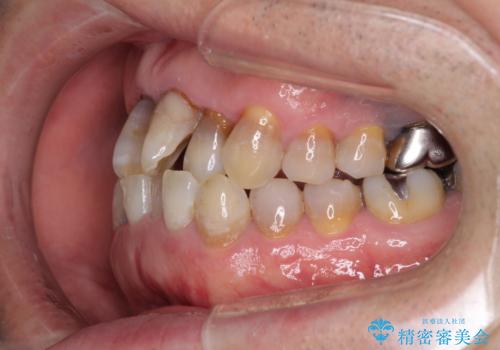

上顎の狭窄歯列 インビザラインによる拡大矯正

- 前歯の叢生と臼歯のクロスバイトを気にして来院された患者様です。

急速拡大装置による上顎の側方拡大を行い、その後はインビザラインより歯列を改善することとしました。

20代後半以降の男性は上顎骨の側方拡大処置の成功率が低く、今回も骨を拡大することができませんでした。

しかしながら、歯列を側方に拡大することができ、その後はインビザラインにて叢生を解消することができました。